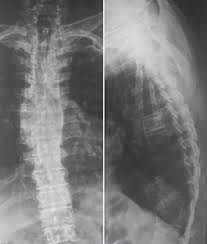

What is an X-ray Dorsal Lumbar Spine AP/Lat?

An X-ray Dorsal Lumbar Spine AP/Lat captures detailed front and side views of the middle and lower spine to detect injuries, deformities, or other abnormalities.

An X-ray Dorsal Lumbar Spine AP/Lat Scan is a medical imaging test that captures detailed front (anteroposterior) and side (lateral) views of the middle (dorsal) and lower (lumbar) parts of your spine. This helps doctors evaluate the bones, joints, and surrounding tissues for injuries, abnormalities, or diseases.

An X-ray Dorsal Lumbar Spine AP/Lat can detect fractures, spinal deformities, degenerative changes, infections, and tumors in the middle and lower spine. It helps doctors assess bone alignment and identify abnormalities for accurate diagnosis and treatment.